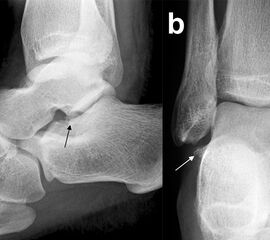

Eine exakte Abgrenzung von Taluskorpus- und Talushalsfrakturen ist allein anhand von Standard-Röntgenaufnahmen nicht sicher möglich. Inokuchi und Mitarbeiter definierten daher Talushalsfrakturen mittels CT, wobei die Frakturlinie distal vor dem Proc. fibularis talis ausläuft 6 (Abb. 1). Es ist anzunehmen, dass sich mit dieser Definition die oben angegebenen Zahlen von den Talushalsfrakturen etwas zu den Taluskorpusfrakturen verschieben, zumal diese mehrheitlich anhand von Röntgenaufnahmen erhoben wurden.

Prinzipiell werden konventionelle Röntgenaufnahmen vom OSG in 2 Ebenen (a.p. in 20° Innenrotation, „Mortise View“, und lateral) angefertigt (Abb. 1a, b). Zusätzlich können spezielle Projektionen wie die Canale oder Brodén-Aufnahme hilfreich sein, wurden in der klinischen Routine aber durch das CT oder DVT weitgehend verdrängt.

Bei in den konventionellen Aufnahmen nicht sicher auszuschließender Talusfraktur bzw. zur genauen Darstellung der Dislokation bei Taluskorpus- oder Talushalsfraktur sollte die Indikation zur CT-Diagnostik großzügig gestellt werden (Abb. 1 c, d). Insbesondere dient die CT-Diagnostik zur genauen Evaluierung der Frakturmorphologie und OP-Planung sowie auch zur Vermeidung möglicher übersehener peripherer Talusfrakturen 4.